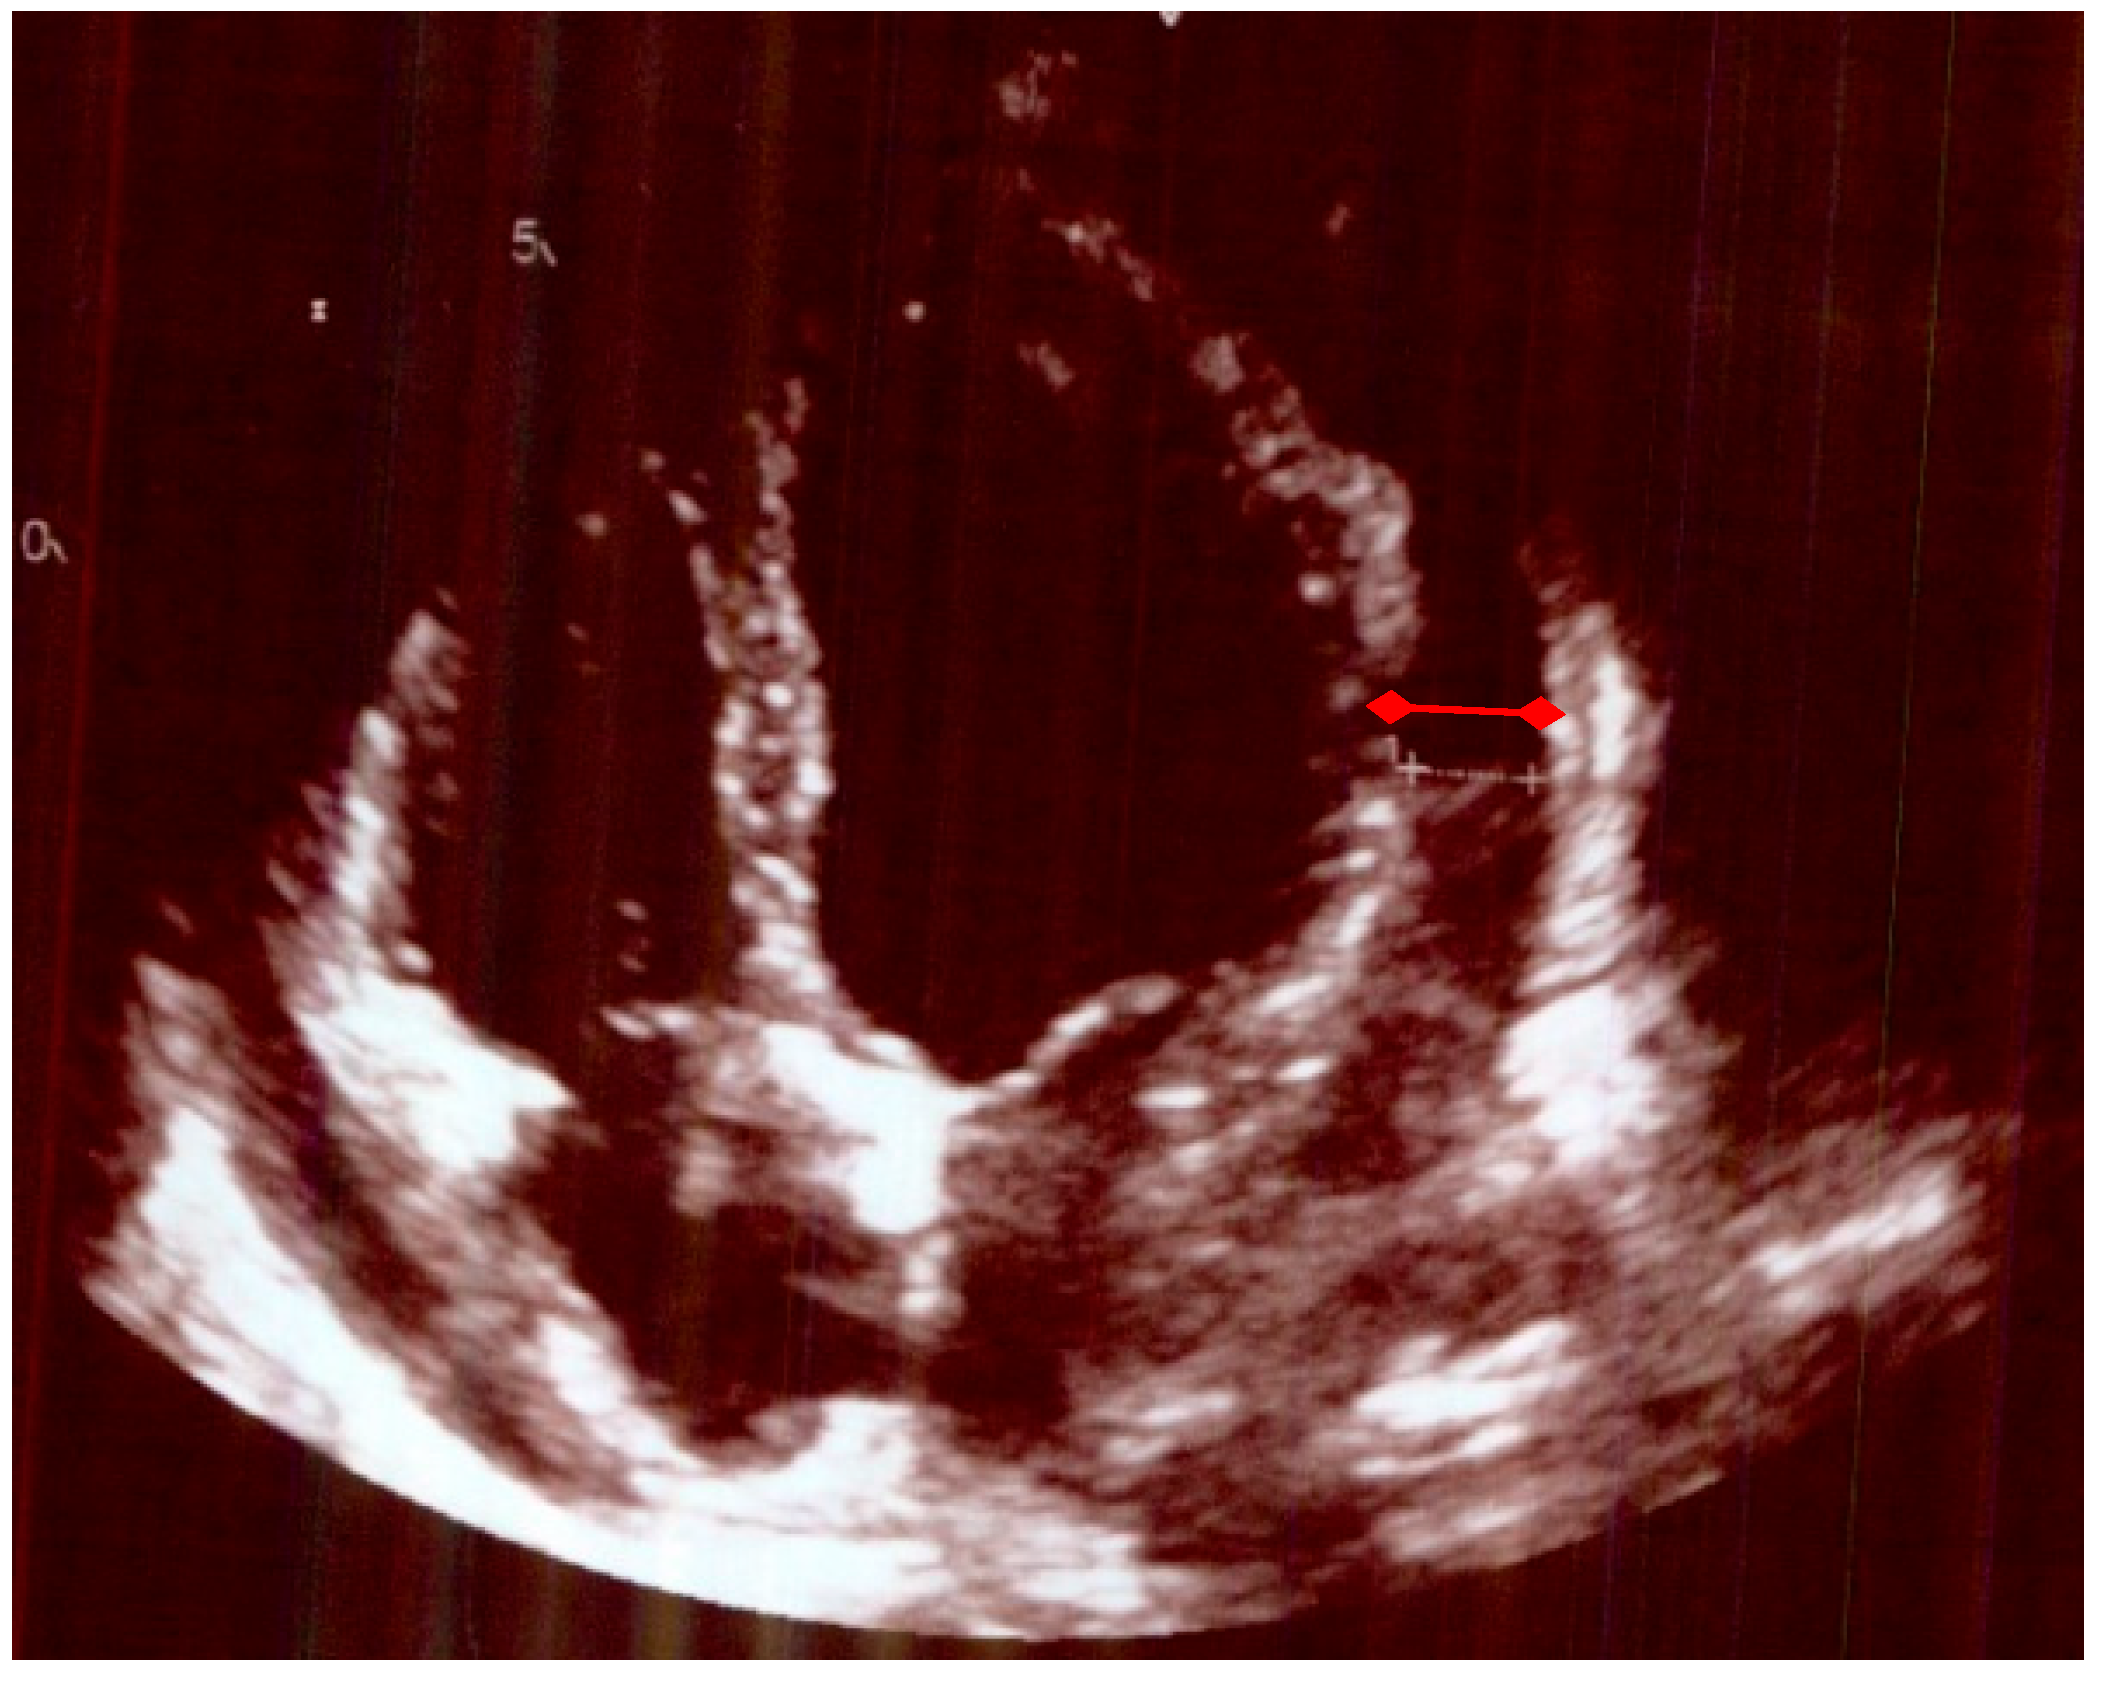

| Echocardiogram Pre-Treatment | Echocardiogram Post-Treatment after 4 Months. |

|---|---|

| A small/moderate global pericardial effusion Normal LV structure and function. Valves appeared structurally and functionally normal Mobile atrial septum, no shunt seen. No evidence of subacute bacterial endocarditis | No obvious residual pericardial effusion Normal LV structure and function No evidence of valve thickening but mild dilation of the non-coronary sinus of Valsalva and trivial AR and MR Normal RV structure and function |